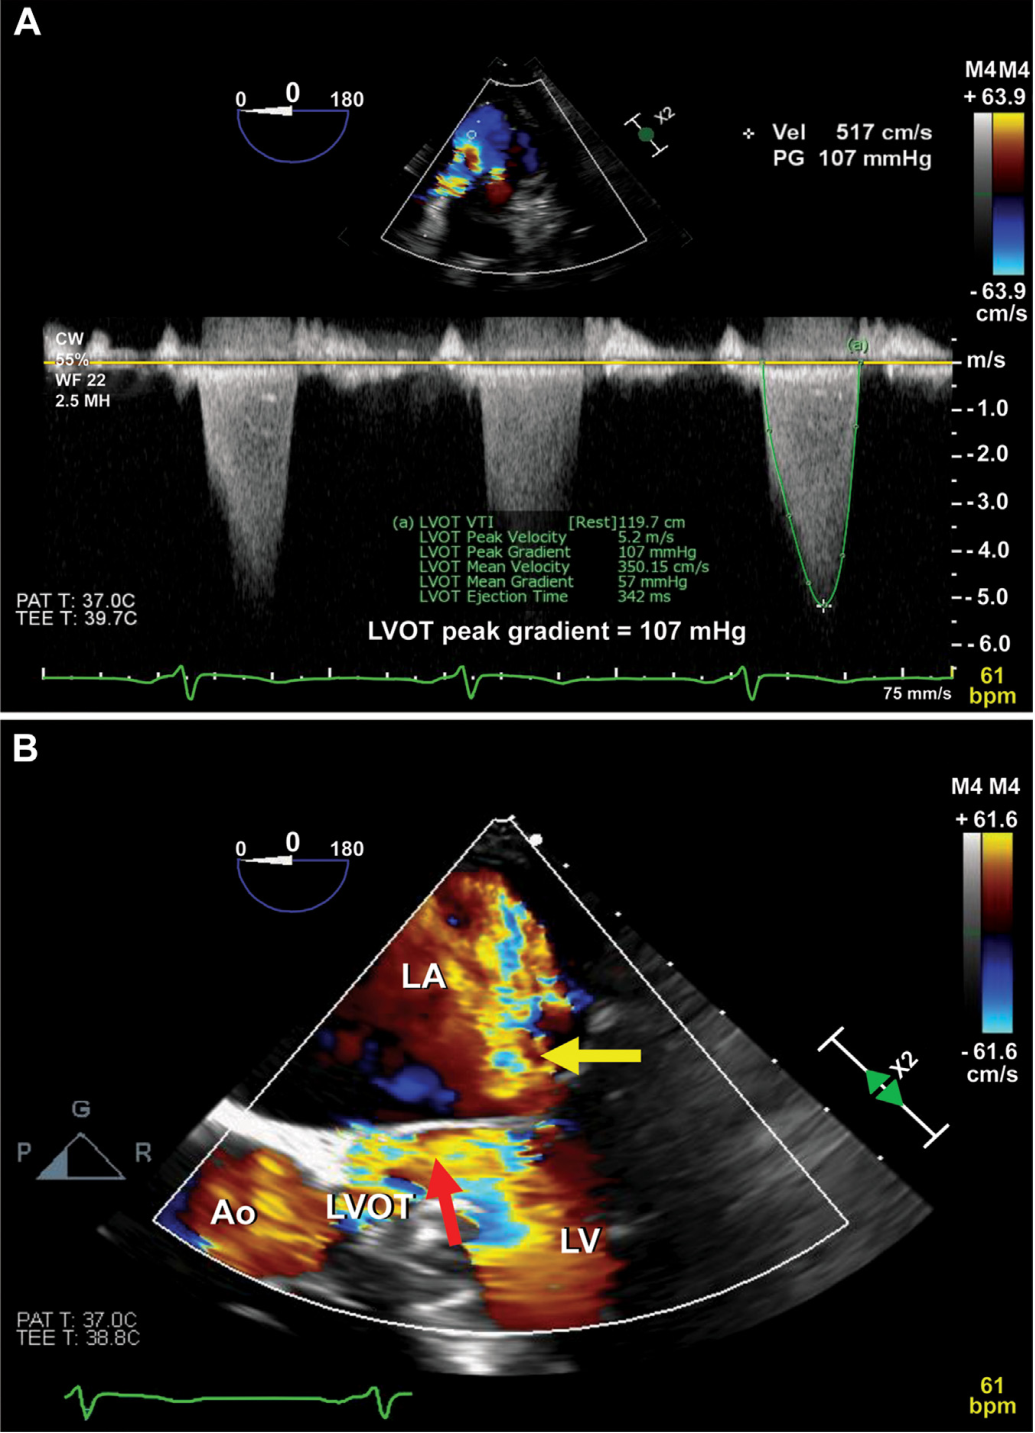

经食道超声示二尖瓣叶增厚,收缩期前向运动(SAM),中-重度二尖瓣反流,动态LVOTO峰值压差107mmHg(图1)。

图1 酒精室间隔消融术前经食管超声心动图

(A)严重LVOTO,峰值压差107mmHg,呈特征性“匕首形”表现;(B)可见二尖瓣前叶SAM(红色箭头),伴中-重度二尖瓣反流(黄色箭头)。Ao=主动脉;LA=左心房;LV=左心室。